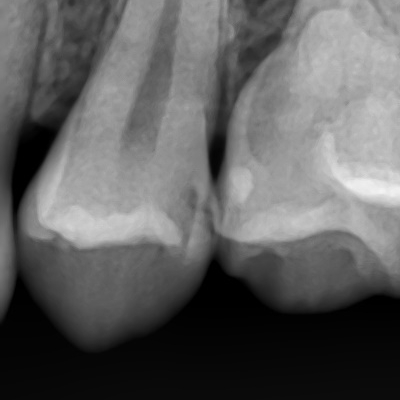

겉에서는 크게 보이지 않지만 치아를 삭제해보면 깊은 충치

환자분이 보기에는 겉에서는 특별히 검게 보이지 않지만

치아를 삭제해보면 깊은 충치인 경우가 많습니다.

엑스레이와 눈으로 보는 시진을 바탕으로 원장님의 검진에 따라 어떤 치료가 진행될지 결정됩니다.

저희 치과는 충치가 깊은 경우 치료 전과 치료 중간중간 구강내 사진을 많이 찍는데요

환자분께 이런 부분에 충치가 깊게 있었다 설명드리고,

치료 후에도 환자분이 관리할 수 있게 만들기 위해서 입니다.